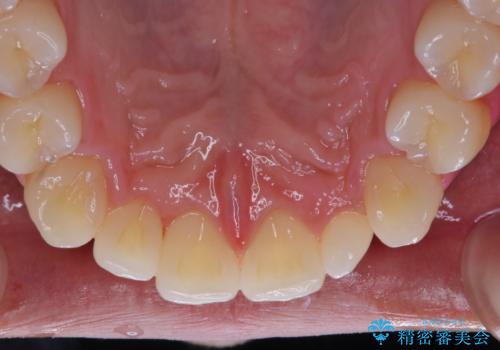

今後、ホームホワイトニング予定との事で、クリーニングPMTC(保険適応外)60分コースを行いました。汚れを取り除き、ご自身の本来の歯の表面になることでツヤがでます。

歯の表面に汚れがついたままホワイトニングを行うと、ホワイトニングの効果が出づらいことがあります。

ホワイトニングご希望の場合は、まずクリーニングを行うことをおすすめします。

汚れがついたままだと、虫歯・歯周病・口臭などの原因にもなります。歯科医院での、定期的なクリーニングを行うことが大切です。